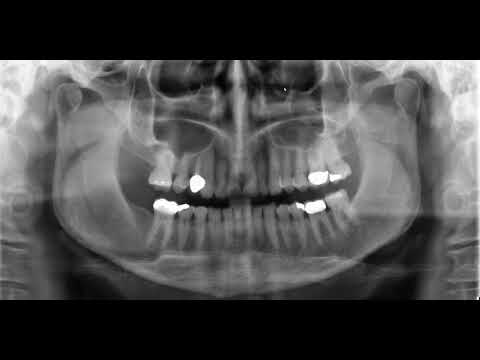

Anatomical Landmarks Found in a Panoramic Radiograph

Panoramic Radiographic Anatomy

PanoAnatomy: Learning Panoramic Anatomy & Radiographic Landmarks

Comprehensive panoramic anatomy review